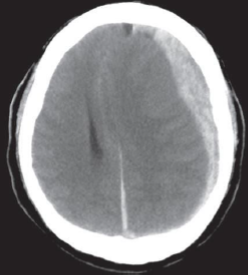

Um homem de 77 anos foi levado ao prontosocorro pelo Serviço de Atendimento Móvel de Urgência, sem resposta, após uma queda de mesmo nível. Na admissão, estava sonolento, não obedecia a comandos e apresentava paralisia de 3º nervo craniano esquerdo, com midríase. Ele tinha histórico de fibrilação atrial. A seguir está sua Tomografia Computadorizada de crânio. Qual das seguintes alternativas corresponde à melhor intervenção terapêutica?